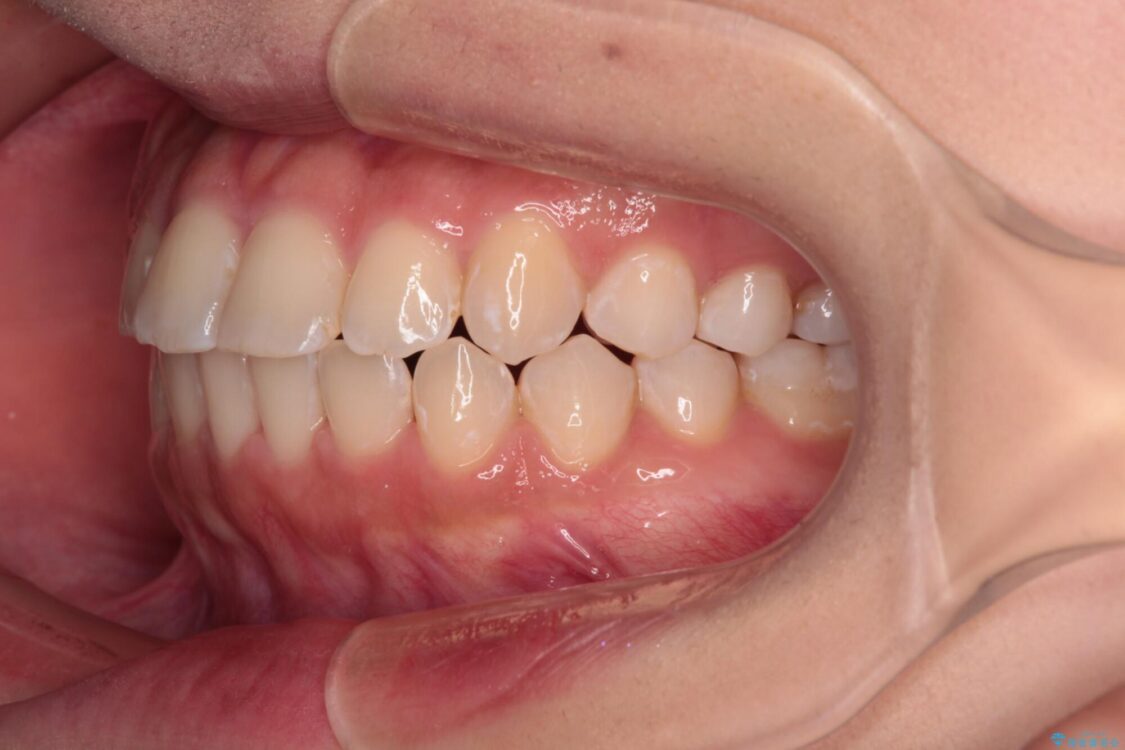

治療後

• 【モニター】短期間で終わりたい ワイヤー装置での非抜歯矯正 治療後画像

当初予定通り、1年で治療を終えることができました。